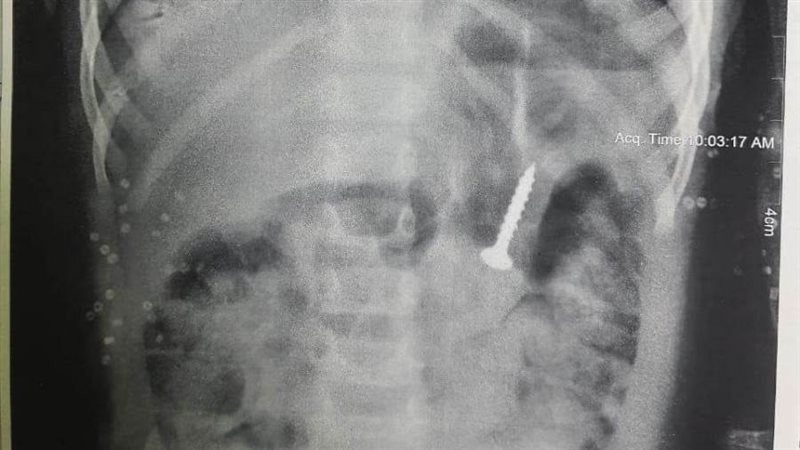

وقال المستشفى في بيان صادر عنه، إن وحدة الجهاز الهضمي ومناظير الأطفال استقبلت طفلة تبلغ من العمر عامين، مصابة بحالة إعياء، وبعد عمل أشعة على المعدة تبين وجود جسم غريب "مسمار".

وأضاف البيان، أن الطفلة ابتلعت الجسم بالخطأ، وجرى استخراجه باستخدام تقنية المنظار دون تدخل جراحي، ووضع الحالة تحت الملاحظة.